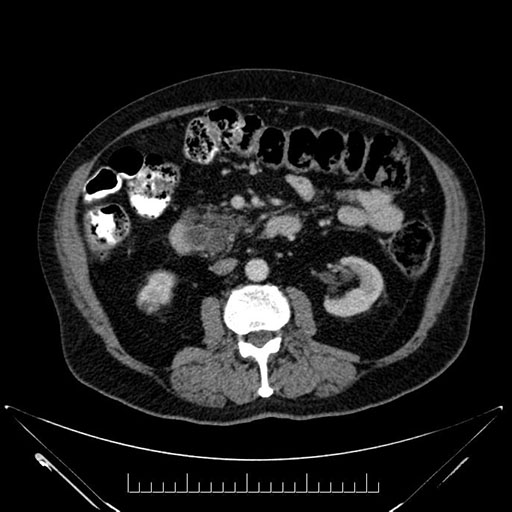

Axial - stented